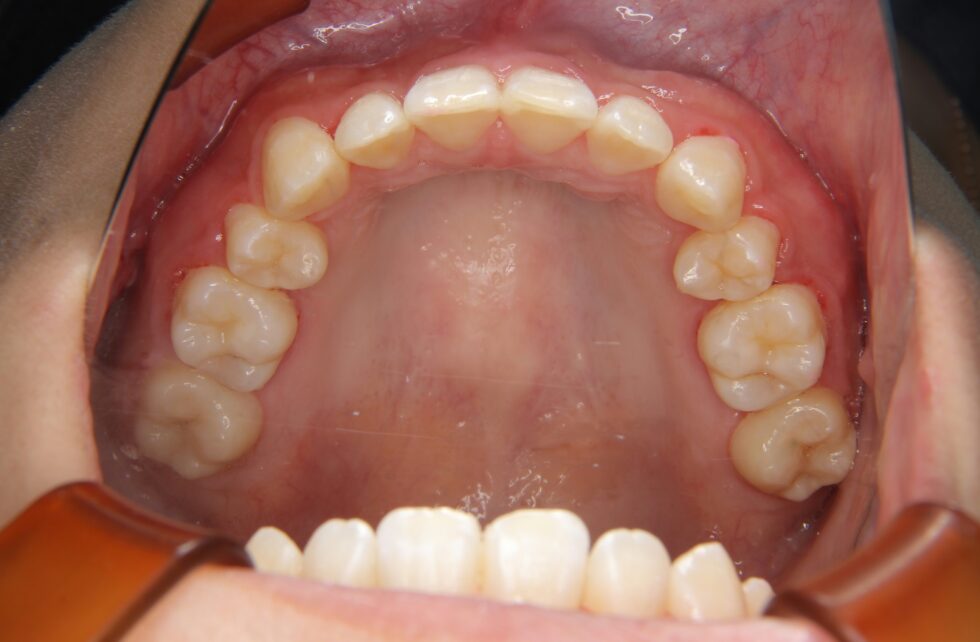

初診時年齢24歳の女性 上顎前歯の内傾を主訴にご来院いただいた。長年、前歯が内側を向いていることを気にされていたが治療を行う勇気が出なかったとのことであった。しかし、咬合時に上顎前歯に痛みを感じるようになったことから治療を希望された。セファログラム他の分析から咬合力の極めて強いと考えられる骨格をされていることが分かった。上あごの前歯が内側を向いた骨格性上顎前突で、アングルの分類Ⅱ級2類と診断した。咬合力が強いと歯の動きは緩徐で、前歯のかみ合わせが深くなり、上あごの前歯の後退が困難になる場合がある。このため、上顎左右側小臼歯を抜歯していただき、矯正用アンカープレートを併用して、上下顎マルチブラケット装置を使用して動的治療を行った。内側を向いていた上顎前歯は適正な角度とすることができた。